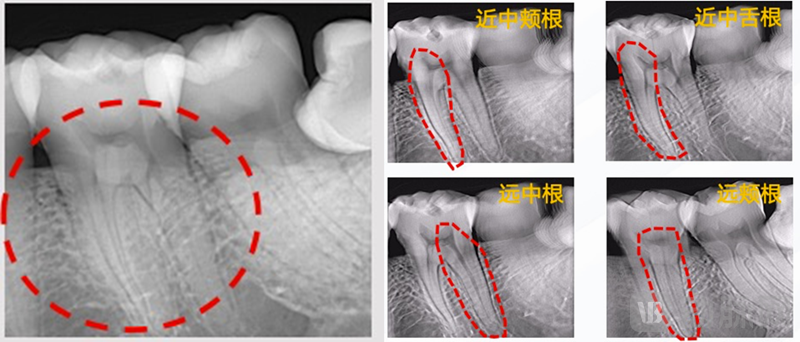

口内X射线成像检查(俗称牙片机)是目前口腔临床中应用最为普遍的检查方法之一,但现有牙片机采用透视成像技术,存在结构混叠、易误诊、漏诊等问题,并经常拍摄失败、需要重复拍片。

新鸿电子的口内低剂量3D成像系统正是从上述痛点问题出发,能在相同图像分辨率和相近辐射剂量水平的基础上,从多个角度对牙齿组织进行超快速扫描,实现无任何机械运动的静态三维成像。和现有牙片机相比,全新的“3D”牙片机图像带来了更加丰富的三维成像细节,对患者的口腔状况进行更清晰、全面的展示,更好地识别咬合面及邻位龋齿、根部骨折、表面损伤与裂缝及变异的细小根管等细微牙齿病灶,帮助医生实现更加精准、高效、安全的诊断,使得疾病的诊疗准确率大幅提升。